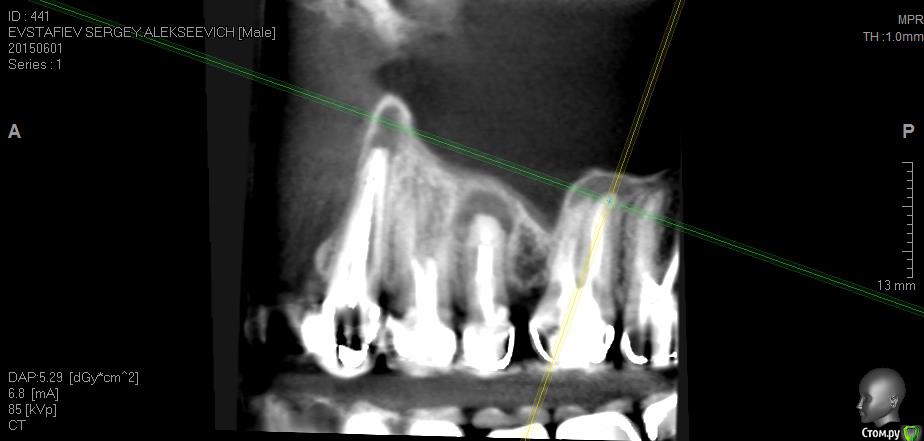

Evstafjev Опубликовано 25 октября, 2015 Поделиться Опубликовано 25 октября, 2015 (изменено) Здравствуйте уважаемые форумчане! Возможно пишу не в ту ветку форума, но мне кажется что эта самая близкая.Приключилось со мной настоящая беда. Расскажу по порядку.Лет 5 назад в виду совсем плохой ситуации с зубами мне предложили и воплотили следующую методику лечения: депульпировали все зубы и покрыли металлокерамическими коронками. Каналы пломбировали гутаперчей, и укрепили титановыми штифтами. Я был безмерно счастлив. Во первых что через все это "прошел" во вторых что стал нормальным человеком с красивой улыбкой и с возможностью "жевать полным ртом".Но с одним зубом у меня всетаки возникла проблема. Года через 2 после лечения заболел сильно верхний 5-й зуб. Я пошел к врачу, ничего особого не заметили и сказали пропить курс антибиотиков а потом придти снова. Я пропил, зуб прошел, плюс обстоятельства сложились, и я не пришел к врачу. Все было хорошо. Но через какое то время (довольно продолжительное) я заметил небольшую шишечку у проблемного зуба на десне. Это оказался свищ. Абсолютно не беспокоил, поэтому я его не сразу и заметил. Этим летом, в виду переезда на постоянное место жительство в другой город, я решил что нужно перед отъездом решить вопрос с зубом. Пошел к врачу, там посовещались и решили что дабы не разбирать конструкцию попробуют сделать резекцию верхушки корня. Отправили на КТ. Сделал КТ 5х5 и увидел что у соседних зубов на корнях также "шишки". Испугавшись сделал КТ всей полости, и о ужас..... на каждом зубе есть такие же "шишки"!!! Прилагаю снимки сделанные из программы КТ, так как все содержимое диска с КТ сюда не поместить, если только через файлообменник, но объем большой и врятли кто то захочет скачивать.Врачи толком ничего не говорят. Сами озадачены. Сказали что раз картина тотальна то то что они плохо пролечили исключено, а что это реакция организма. Решили пока в качестве эксперимента пролечить через канал проблемный 5-й зуб. Протезист сказал что штифты выкручиваются без проблем. Распилил коронку вывернул штифт и далее терапевт начал лечение используя физиопроцедуры с током. Лечили 2-3 месяца. Запломбировали гутаперчей и закрыли временной пломбой. Сказали нужно хорошенько подождать чтобы понять помогло ли лечение. Вот на днях будут смотреть что вышло.Подскажите уважаемые специалисты, каково Ваше мнение по ситуации. Так прискорбно понимать что я в 36 лет похоже лишился всех зубов...PS:Пока лечили зуб параллельно у меня заболели зубы на нижней челюсти. Делали разрез, пил антибиотики - кошмар. Изменено 25 октября, 2015 пользователем Evstafjev Ссылка на комментарий

Evstafjev Опубликовано 26 октября, 2015 Автор Поделиться Опубликовано 26 октября, 2015 Я вот думаю что фото из КТ не полностью показывают картину, не очень я владею данным программным обеспечением, с трудом поймал ракурс. Но не очень информативно. Если крутить мышкой отдельно у каждого зуба тот там картинка "пострашнее" Ссылка на комментарий